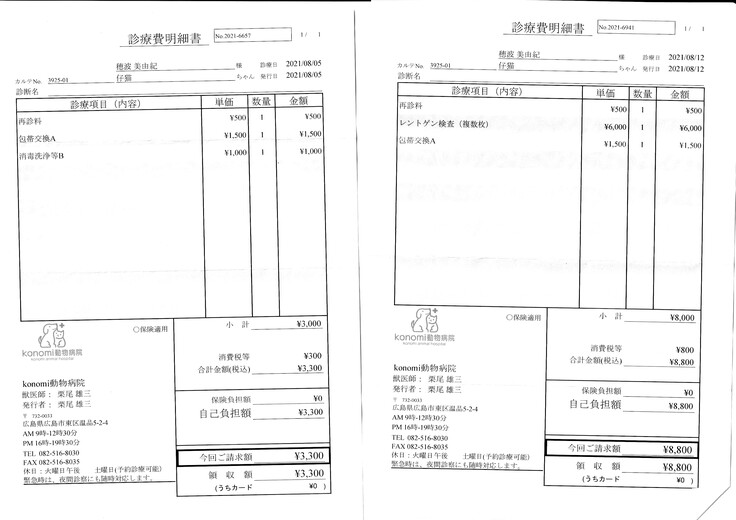

明細書

①入院費用

②退院後の飼育と治療

治療は続いていますが、これまでにかかった費用の一部を皆さまに助けて頂きたく、宜しくお願い致します。